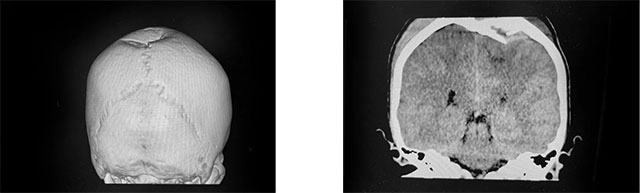

▲ CT影像显示,小宝顶骨大块凹陷性骨折,脑顶叶皮层受压

小宝被收治入院后,神经外科6A病区医生团队第一时间为患者开展了全面的检查,并采取了降颅压等治疗措施。CT检查报告很快出来了,患者两侧顶骨(左侧为主)大块凹陷性骨折(约5cm*6cm),下陷约2cm,脑顶叶皮层受压、凹陷,骨折区域硬膜外、脑表急性期血肿,左侧幕上轻度高颅压。由于损伤部位涉及脑部重要功能区,需通过手术,减轻颅骨骨折压迫,清除颅内血肿并修复受损的颅骨,防止可能出现的脑神经功能损伤。